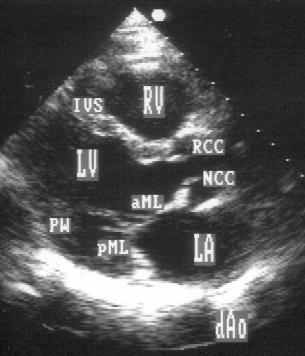

Парастернальная позиция длинной оси левого желудочка (рис. 2.1А,B)

В.Рисунок 2.1. Парастернальная позиция длинной оси левого желудочка с оптимальной визуализацией митрального клапана (А) и аортального клапана (В). LV — левый желудочек, RV — правый желудочек, Ao — корень аорты и восходящий отдел аорты, LA — левое предсердие, IVS — межжелудочковая перегородка, PW — задняя стенка левого желудочка, dAo — нисходящий отдел аорты, CS — коронарный синус, RCC — правая коронарная створка аортального клапана, NCC — некоронарная створка аортального клапана, aML — передняя створка аортального клапана, NCC — некоронарная створка аортального клапана, aML — передняя створка митрального клапана, pML — задняя створка митрального клапана.

Датчик устанавливается слева от грудины в третьем, четвертом или пятом межреберье. Центральный ультразвуковой луч (продолжение длинной оси датчика) направляется перпендикулярно поверхности грудной клетки. Датчик поворачивается таким образом, чтобы его плоскость была параллельна воображаемой линии, соединяющей левое плечо с правой подвздошной областью. Для получения оптимального изображения длинной оси левого желудочка часто требуется отклонение плоскости датчика примерно на 30° (центральный луч направлен в сторону левого плеча). Эта позиция рассекает левый желудочек от верхушки до основания. Аорта должна находиться в правой части изображения, область верхушки левого желудочка — в левой.

Ближе всего к датчику находится передняя стенка правого желудочка, за ней — часть выносящего тракта правого желудочка. Ниже и правее расположены корень аорты и аортальный клапан. Передняя стенка аорты переходит в мембранозную часть межжелудочковой перегородки, задняя стенка аорты — в переднюю створку митрального клапана. Кзади от корня аорты и восходящего отдела аорты находится левое предсердие. Задняя стенка левого предсердия — это в норме самая удаленная от датчика структура сердца в данной позиции. Кзади от левого предсердия часто обнаруживается эхо-негативное пространство овальной формы. Это — нисходящая аорта; овальная ее форма обусловлена тем, что срез проходит под острым углом как к длинной, так и к короткой ее оси. Задняя стенка левого предсердия переходит в атриовентрикулярный бугорок и затем в заднюю стенку левого желудочка. В области атриовентрикулярного бугорка часто видна эхо-негативная структура округлой формы; это — коронарный синус. При расширении коронарного синуса его можно ошибочно принять за нисходящую аорту. Впрочем различить эти структуры нетрудно: коронарный синус движется вместе с митральным кольцом, а нисходящая аорта, будучи структурой внесердечной, вместе с сердцем не движется. Задняя стенка левого желудочка визуализируется от уровня митрального кольца до папиллярных мышц; направив центральный ультразвуковой луч книзу, можно расширить область визуализации задней стенки левого желудочка. Верхушка левого желудочка находится на одно или несколько межреберий ниже датчика, установленного парастернально, и в срез не попадает, так что не следует пытаться судить о локальной сократимости верхушечных сегментов левого желудочка из этой позиции. Кпереди от задней стенки левого желудочка находится полость левого желудочка, в норме самая большая из всех структур в этой эхокардиографической позиции. В полости левого желудочка визуализируются передняя и задняя створки митрального клапана. Межжелудочковая перегородка, ограничивающая полость левого желудочка спереди, видна от мембранозной части до области, прилежащей к верхушке левого желудочка.

Структуры, представляющие в этой позиции наибольший интерес, — межжелудочковая перегородка, аортальный и митральный клапаны — обычно не могут быть идеально видны на одном изображении. Поэтому требуется оптимизация изображений отдельных структур. Длинная ось восходящей аорты обычно находится под углом 30° к длинной оси левого желудочка, поэтому для оптимальной визуализации восходящей аорты, корня аорты и аортального клапана нужно слегка повернуть датчик. На рис. 2.1B представлена позиция парастернальной длинной оси левого желудочка, оптимизированная для наилучшей визуализации аортального клапана. Плоскость датчика повернута таким образом, чтобы диаметр корня аорты и восходящего ее отдела был максимальным. Это позволяет исследовать размеры аорты и максимальное раскрытие створок аортального клапана.

Для оптимальной визуализации митрального клапана плоскость датчика отклоняют вперед-назад до тех пор, пока не будет получена позиция, в которой створки митрального клапана раскрываются максимально (рис. 2.1A). Плоскость сечения левого желудочка должна при этом проходить между папиллярными мышцами, так чтобы ни они, ни хорды не попадали в изображение. Эта позиция соответствует максимальному переднезаднему размеру левого желудочка на уровне его основания.